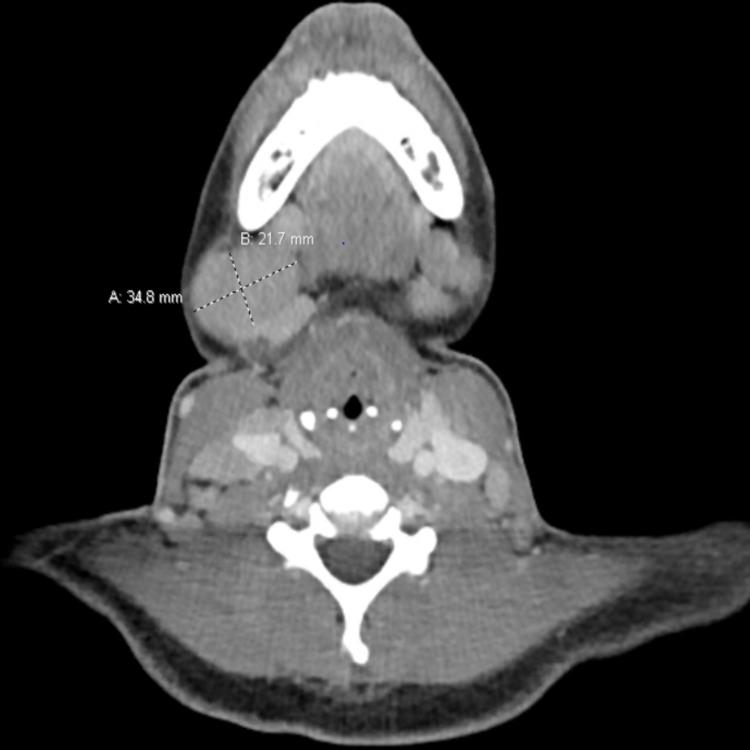

Adult-onset Still's disease (AOSD), a rare systemic inflammatory disorder of unknown etiology, is considered in broad differential in patients with fever of unknown origin or unexplained lymphadenopathy. It is characterized by spiking fever, evanescent salmon-colored maculopapular rash, arthritis or arthralgia, and leukocytosis. Due to broad differentials and lack of any specific diagnostic tests, diagnosis of AOSD poses a great challenge. A concerned physician should have a high index of suspicion while dealing with patients presenting with clinical symptoms of this systemic disorder. We report a case of a 25-year-old African American female with the past medical history of AOSD, who presented with four weeks history of extensive cervical and axillary lymphadenopathy mimicking lymphoproliferative malignancy. Cases have been reported with the development of malignant lymphoma during the course of AOSD. Therefore, careful monitoring of patients with regular follow-up is vital as these patients may develop lymphoproliferative malignancy in the future.

成人斯蒂尔病(AOSD)是一种病因不明的罕见全身性炎症性疾病,在不明原因发热或不明原因淋巴结病的患者鉴别诊断中需广泛考虑。其特征为高热、一过性的鲑鱼色斑丘疹、关节炎或关节痛以及白细胞增多。由于鉴别诊断范围广泛且缺乏任何特异性诊断试验,AOSD的诊断极具挑战性。在诊治出现这种全身性疾病临床症状的患者时,相关医生应保持高度怀疑。我们报告一例25岁非裔美国女性,既往有AOSD病史,此次因广泛的颈部和腋窝淋巴结病长达四周就诊,酷似淋巴增殖性恶性肿瘤。已有报道称在AOSD病程中会发生恶性淋巴瘤。因此,对这些患者进行定期随访的仔细监测至关重要,因为他们未来可能会发生淋巴增殖性恶性肿瘤。